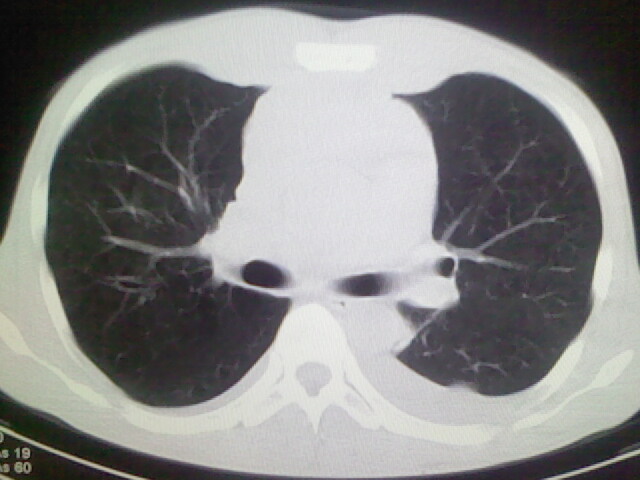

以下是引用杀毒软件在2008-9-3 6:11:00的发言:[br]侵袭性胸腺瘤------一般不侵到气管旁[br][br]考虑----纵隔淋巴瘤,心包及胸膜受累

以下是引用随光逐影在2008-9-3 7:07:00的发言:[br]1)考虑淋巴瘤可能。2)双侧胸腔积液(以左侧为甚)。3)心包积液。